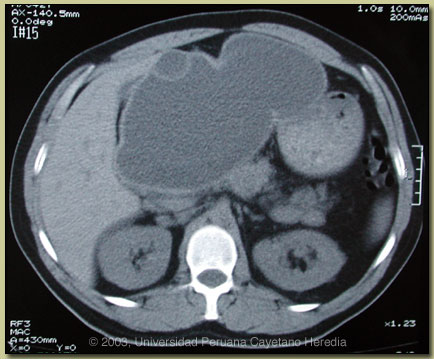

| Diagnosis: Massive hydatid cyst due to Echinococcus granulosus. |

CT scan of the abdomen (see image at right) showed an uncomplicated 15 cm hepatic cyst with contents of liquid density replacing the left lobe of the liver. There is a small daughter cyst anteriorly. The endocyst and pericyst membranes are intact and without calcification. These CT findings indicate an active growing lesion with viable echinococcal scoleces in the contents. ELISA for E. granulosus was positive at 1.76 OD units (normal <0.5). Arc V immunodiffusion (higher specificity diagnostic test than ELISA) was also positive. Human hydatid disease secondary to Echinococcus granulosus is caused by the larval form of this dog tapeworm. Humans ingest the tapeworm eggs in environments contamined by canine feces and become accidental intermediate hosts. Sheep are the normal intermediate hosts. Larval cysts expand slowly over years or decades becoming symptomatic as they impinge on other structures by virtue of their size. The cysts contain hundreds of viable scoleces capable of becoming adult tapeworms upon ingestion by a definitive host such as the dog. The germinal membrane lining the cyst produces new scoleces on an ongoing basis. Each scolex is capable of becoming a new daughter cyst either within the original cyst or elsewhere should the original cyst rupture or be ruptured. Hydatid disease is common in sheep-raising areas worldwide. Most primary infections involve a single cyst. 65% of solitary cysts are found in liver, 25% in lung and the rest in a wide variety of other organs including kidney, spleen, heart, bone and brain. In patients with a pulmonary cyst, approximately 15% will also have a hepatic cyst. A primary hydatid cyst palpable on physical examination, such as is seen with our patient, is uncommon. Serology is usually positive with hepatic cysts but sensitivity drops below 50% with solitary pulmonary cysts even when the cyst is large. Possible treatment options in this case would include observation, medical therapy alone with albendazole, percutaneous drainage, or complete surgical resection. Observation of this superficial and very large cyst would carry the significant chance of a catastrophic rupture (with seeding of the peritoneum with viable scoleces) due to incidental blunt trauma. Medical therapy alone has had 30-70% success rates in various case series but success is most often with cysts less than 10 cm and many studies have excluded larger cysts such as this. Although there is little published data, it is the experience of many clinicians who have treated large numbers of patients that albendazole therapy of large tense cysts such as this significantly softens the capsule increasing the risk of spontaneous rupture or of slow leakage (can cause anaphylaxis). Percutaneous Aspiration Instillation (of a scolicidal solution) and Reaspiration (PAIR procedure) is increasingly used and recommended worldwide for uncomplicated cysts. This procedure is not currently available in Perú but would likely be the procedure of choice in an area where an experienced operator was available. Given the large size (>10 cm) of the cyst, we have recommended surgical resection which should be straightforward given the location of his cyst. Perioperative coverage with albendazole should be considered to cover the possibility of intraoperative spills. Nevertheless, some surgeons are reluctant to do this because of a feeling that albendazole softens the cyst wall and makes the surgery more difficult. Most surgeons inject hypertonic saline or other scolicidal agent (e.g., cetrimide) intraoperatively prior to cyst removal to kill viable scoleces. This should not be done in cases where there is any chance of the cyst having eroded into the biliary tree as the scolicidal agent will induce a sclerosing cholangitis.